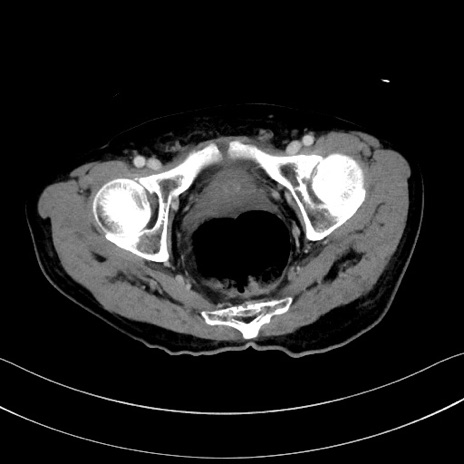

冠状断像

【症例】60歳代男性

【主訴】嘔吐

【現病歴】胃癌にて胃全摘後。食思不振が悪化し、夜中に嘔吐することがある。

【既往歴】胃癌、胃全摘、脾摘、胆摘後

【データ】WBC 5900、CRP 10.56